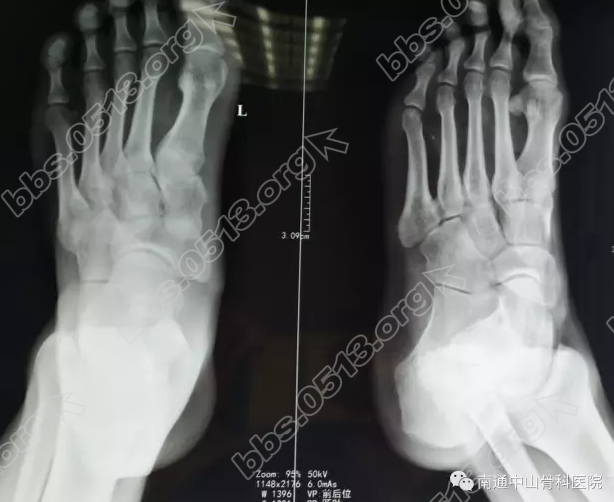

手术后,科室制定了严密的治疗护理计划,包括营养支持、预防感染、肢体功能锻炼、饮食管理等一系列措施,使患者手术后恢复的更快。8 J9 A8 [; U' r5 ?

3 U4 s* t0 {) D4 T& B* A4 S* h1 N+ z  我院医生每天都要来到病房进行术后康复指导,叮嘱注意事项同时还经常鼓励患者为他进行心理辅导消除患者消极心态。在一段时间的精密护理后,恢复效果还是很明显的。在病房里,我们可以看到从他的脸上露出了久违的笑脸,胡某的父母也渐渐放下心来。